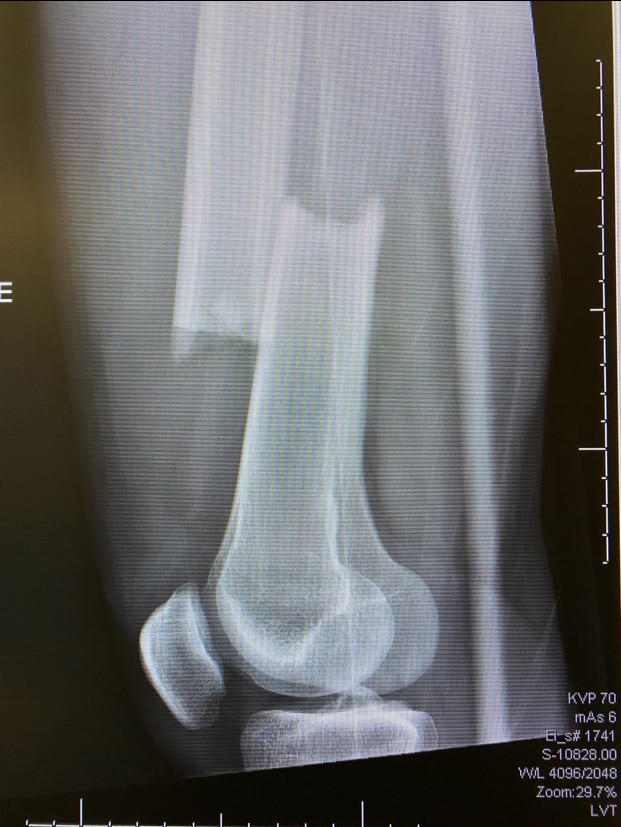

With a minute gone in the second period, Brodzinski skated the puck across the middle of the offensive zone. Eagles forward Trevor Kuntar hustled towards him from the opposite direction. The collision left Brodzinski on the ice, grabbing for his right leg. His femur was completely broken, a clean break.

Easton Brodzinski's broken right femur. Easton Brodzinski's right femur was described as a clean break.